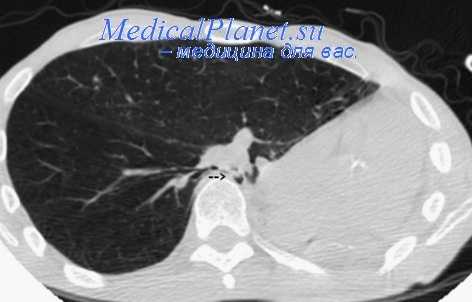

Пневмонэктомия с торакопластикой